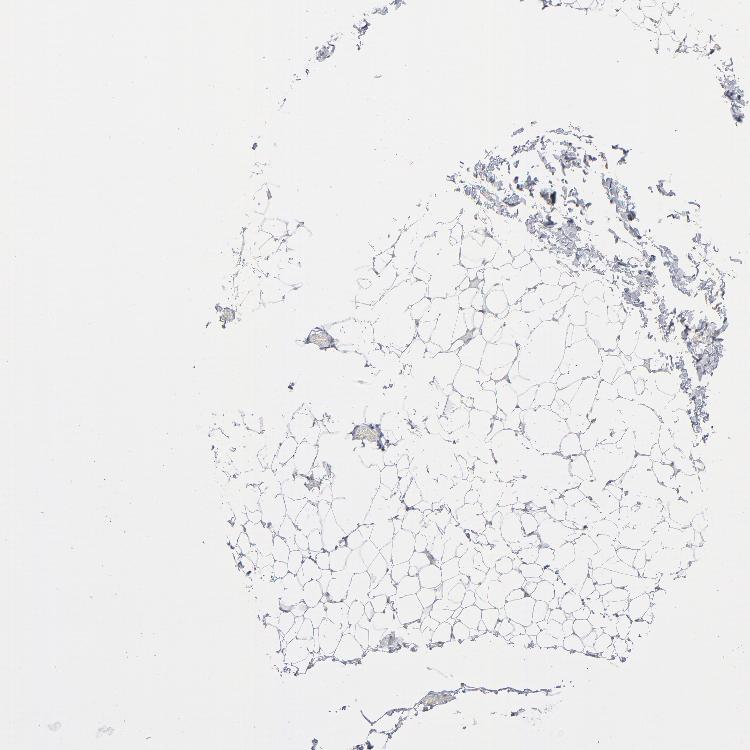

SOFT TISSUE 2 - Antibody stainingi

Antibody staining in the annotated cell types in the current human tissue is reported as not detected, low, medium, or high, based on conventional immunohistochemistry profiling in selected tissues. This score is based on the combination of the staining intensity and fraction of stained cells.

Each image is clickable and will lead to virtual microscopy that enables deeper exploration of all samples and also displays staining intensity scores, fraction scores and subcellular localization as well as patient and tissue information for each sample.

Antibody HPA035330Antibody CAB003677

Fibroblasts HighNot detected

Peripheral nerve Medium-